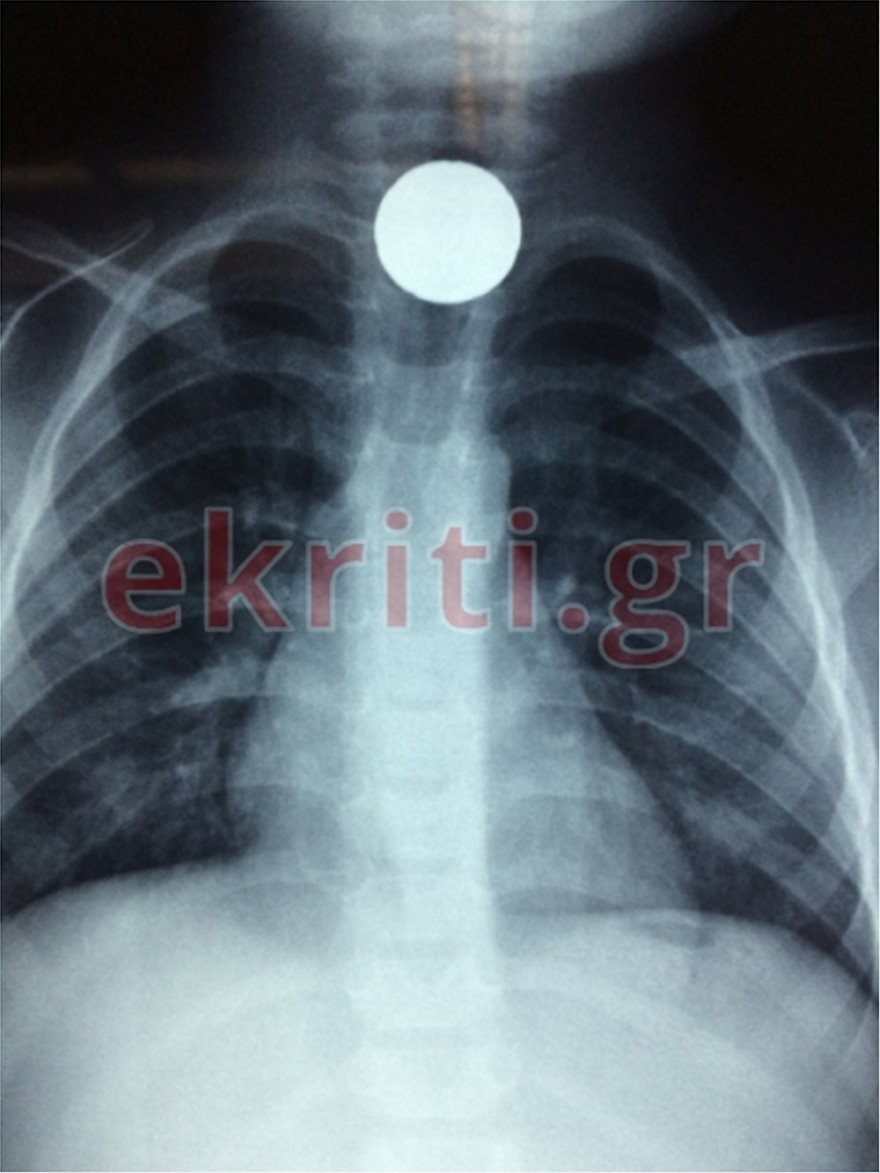

Μια μεγάλη περιπέτεια ζει από το μεσημέρι της Τρίτης ένα αγοράκι μόλις δύο ετών και η οικογένεια του, καθώς κατάπιε ένα… κέρμα.

Το μικρό παιδί, άγνωστο πως κατάπιε το μικρό αντικείμενο (ένα κέρμα 20λεπτο), με τους γονείς του να το μεταφέρουν άμεσα στο Βενιζέλειο νοσοκομείο Ηρακλείου που εφημέρευε. Αφού έγιναν όλες οι απαραίτητες εξετάσεις, αποφασίστηκε να μπει στο χειρουργείο.

Σημειώνεται ότι το κέρμα είχε κολλήσει στον οισοφάγο του μικρού παιδιού.